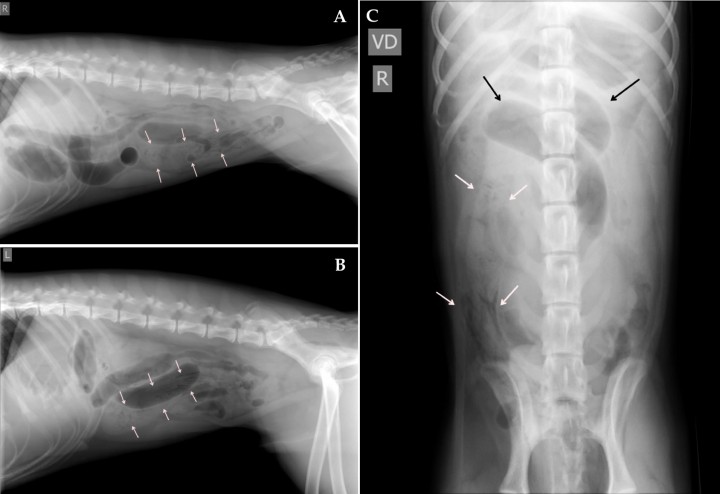

Acude a consulta un cachorro de 7 meses, macho, mestizo que presentaba episodios de vómitos, anorexia y apatía desde hacía 24 horas. El examen físico fue normal y no se observaron alteraciones relevantes en las analíticas sanguíneas. Se realizaron radiografías lateral derecha (Fig. 1A), izquierda (Fig. 1B) y ventrodorsal (Fig. 1C) de la cavidad abdominal.

<p>Radiografías de abdomen. (<strong>A</strong>) Lateral derecha. (<strong>B</strong>) Lateral izquierda. (<strong>C</strong>) Ventrodorsal.</p>

Radiografías de abdomen. (A) Lateral derecha. (B) Lateral izquierda. (C) Ventrodorsal.

Se visualizan varias asas de intestino delgado dilatadas y apiladas localizadas en abdomen craneal y medio, con contenido de opacidad gas y tejido blando en su interior (Fig. 2) y otras que mantienen su tamaño normal. Una de estas asas, localizada entre abdomen medio-caudal (Figs. 2A y B) y en el lado derecho (Fig. 2C), se encuentra dilatada con un ratio de diámetro del asa respecto a altura del cuerpo de la vértebra L5 de 2,8 (ratio normal 1), con un contenido de opacidad tejido blando y presencia de gas dispuesto en un patrón de líneas radiolúcidas y moteado. Este contenido se extiende a lo largo del asa desde la cuarta vértebra lumbar hasta el sacro.

<p>Mismas radiografías que la Figura 1. Se observan varias asas de intestino delgado dilatadas y apiladas localizadas en abdomen craneal y medio, con contenido de opacidad gas y tejido blando en su interior (flechas negras). En abdomen medio-caudal (<strong>A</strong> y <strong>B</strong>) y en el lado derecho (<strong>C</strong>), se visualiza otra asa dilatada con un ratio de diámetro del asa respecto a altura del cuerpo de la vértebra L5 de 2,8, con un contenido de opacidad tejido blando y presencia de gas dispuesto en un patrón de líneas radiolúcidas y moteado (flechas blancas).</p>

Mismas radiografías que la Figura 1. Se observan varias asas de intestino delgado dilatadas y apiladas localizadas en abdomen craneal y medio, con contenido de opacidad gas y tejido blando en su interior (flechas negras). En abdomen medio-caudal (A y B) y en el lado derecho (C), se visualiza otra asa dilatada con un ratio de diámetro del asa respecto a altura del cuerpo de la vértebra L5 de 2,8, con un contenido de opacidad tejido blando y presencia de gas dispuesto en un patrón de líneas radiolúcidas y moteado (flechas blancas).